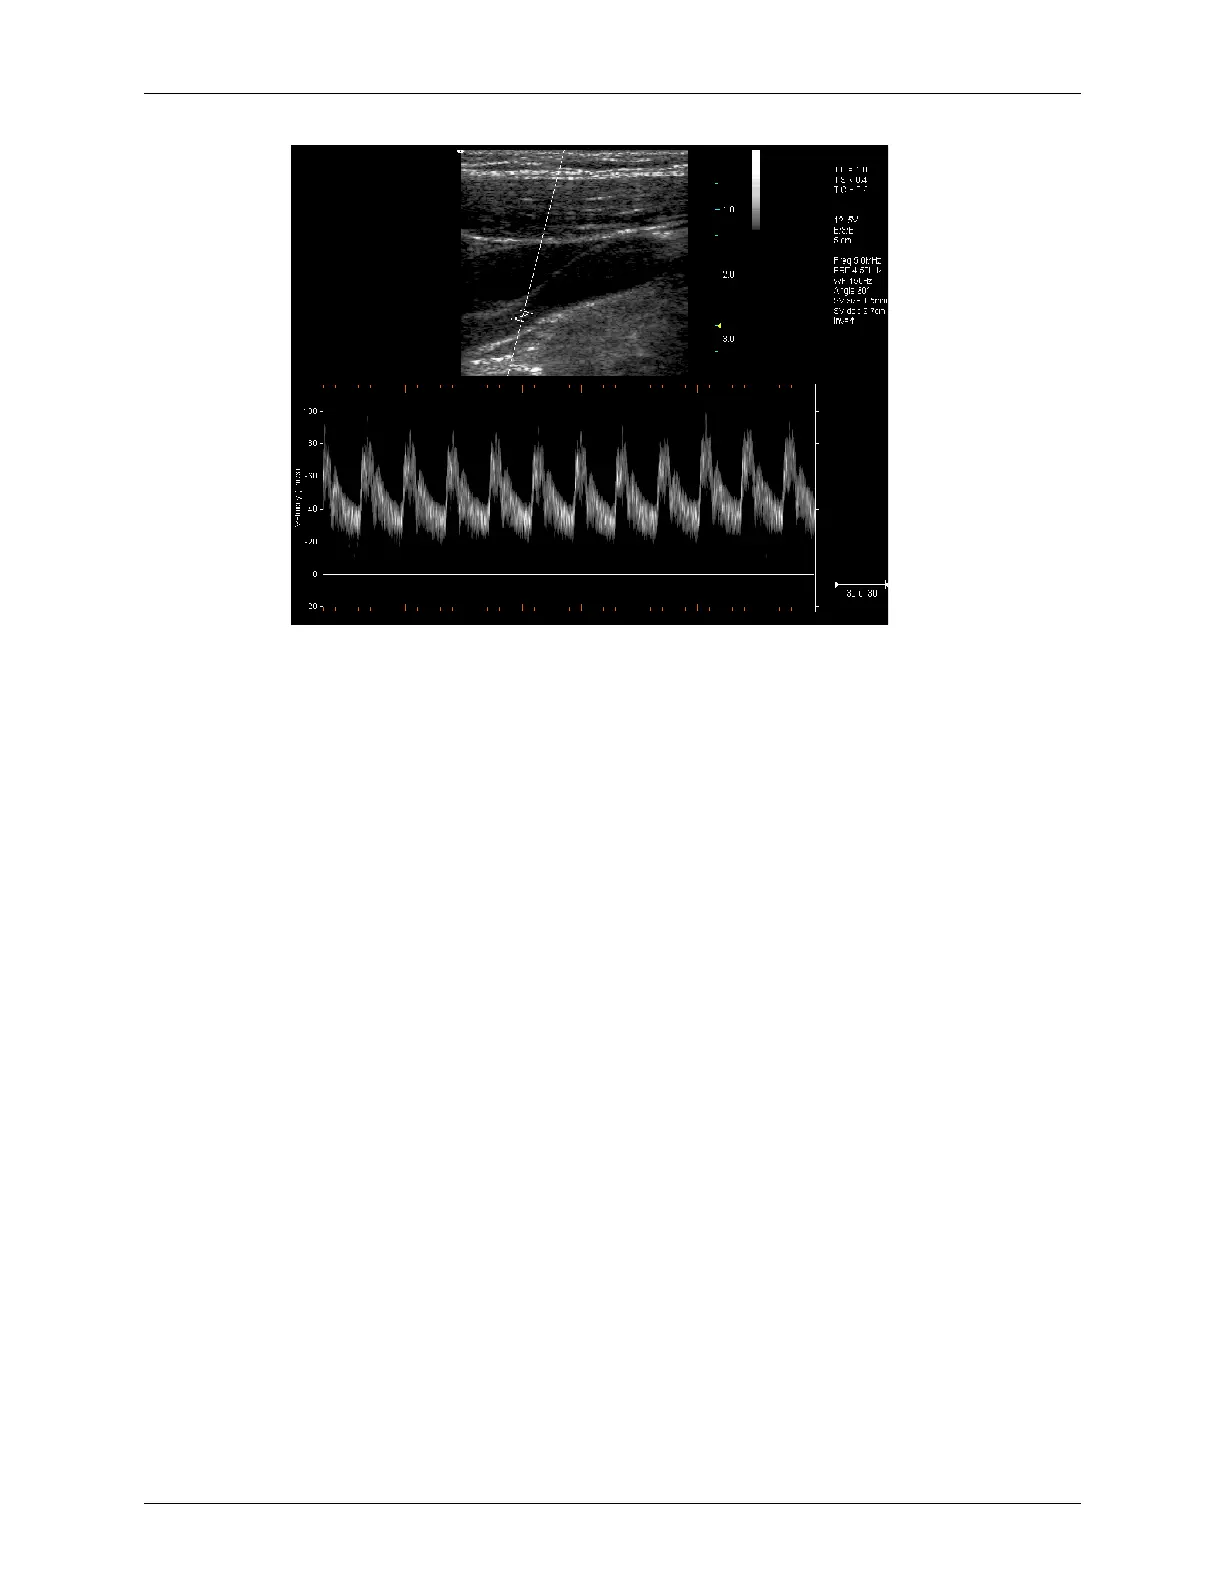

Terason t3000 - Continuous-Wave Doppler; Triplex

Continuous-Wave Doppler

Continuous-Wave Doppler scans display all velocities present over the entire length of the

ultrasound cursor. This is useful for imaging very high velocities such as those resulting

from a leaking heart valve.

As with Pulsed-Wave Doppler scans, the X-axis of the graph represents time, and the Y-

axis represents Doppler frequency shift.

Triplex

Triplex scan mode is available only with the AD version. Triplex scan mode combines

simultaneous or non-simultaneous Doppler imaging (Color Doppler, Directional Power

Doppler, or Power Doppler) with Pulsed-Wave Doppler imaging to view arterial or venous

velocity and flow data. Triplex allows you to perform range-gated assessment of flow.